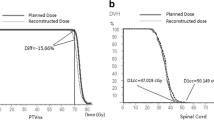

A sample of dose-volume histograms (DVHs) of PTVs, CTVs, and GTVs was shown in Fig. 4. The solid line represented the DVH of the treatment plan, and the 5 dashed lines represented the DVH of U-plans. The envelope was defined as the area between all the DVH curves. The gradually narrowed envelope was seen in PTVp (Fig. 4A), CTVp (Fig. 4D), and GTVp (Fig. 4G). PTVn (Fig. 4B) exhibited high sensitivity to set-up uncertainty. Narrowed width of the envelope was seen in CTVn (Fig. 4E). Sufficient dose coverage and decreased robustness were noticed in GTVn (Fig. 4H). Superior robustness was seen in PTV (Fig. 4C) and CTV (Fig. 4F).

As to OARs (Fig. 5), the brain stem (Fig. 5A) and its PRV (Fig. 5B) exhibited weak robustness due to their locations in the vicinity of PTVs. The spinal cord (Fig. 5C) and its PRV (Fig. 5D) had stronger robustness. Bilateral parotid glands (Fig. 5E. F) were sensitive to set-up uncertainty for their being partially enclosed PTVs. The Dmax of bilateral optical nerves (Fig. 5G–I) and lens(Fig. 5J, K) varied slightly.

A sample of dose-volume histograms (DVHs) of OARs was compared for 1 treatment plan and 5 U-plans. The DVH curve in the solid line represented the treatment plan. The DVH curves in the dashed line represented 5 U-plans. A Brain Stem; B Brain Stem PRV; C Spinal Cord; D Spinal Cord PRV; E Parotid L; F Parotid R; G Optical Nerve L; H Optical Nerve R; I Optical Nerve Chimsa; J Lens L; K Lens R

The TCP reduction (ΔTCP) was the mean absolute value of the minimum value subtracted from the maximum value. For GTVp and CTVp, the ΔTCP value was less than 1% (Fig. 6), indicating strong robustness to set-up uncertainty. A greater ΔTCP value was observed in GTVn and CTVn. CTV had the largest TCP reduction.

We performed NTCP modeling analysis to evaluate the dose variation of OARs (Fig. 7). The NTCP reduction (ΔNTCP) was obtained as the mean absolute value of the minimum value subtracted from the maximum value. The average ΔNTCP of bilateral parotids reached 6.17% (left) and 7.70% (right) (Fig. 7). No significant biological dose changes were found in OARs.

VMAT plans exhibited strong sensitivity to geometric deviation PTVp and PTVn with large ΔD98% and ΔD95%. In photon radiotherapy, the CTV-to-PTV margin method was adopted based on the Van Herk margin formula [16] in the margin-based treatment planning, to ensure the dose coverage of CTV by blurring dose distribution induced by systematic setup errors. Although the CTV-to-PTV margin increased robustness in CTVp and CTVn, the ΔD98% of CTVp and CTVn reached 1.12 Gy and 1.39 Gy. The ΔD98% of GTVp and GTVn reached 0.56 Gy and 0.64 Gy. Similarly, considerable dose deviations were observed in D95% of CTVp, CTVn, PTVp, and PTVn. Although the margin method effectively improved the plan's robustness by reducing sensitivity to the uncertainties, high risk remains. The dose variation of D95% and D98% in PTVs could reach a maximum of 6 Gy. The maximum difference of D95% and D98% in CTVs and GTVs could reach a maximum of 2.81 Gy. The maximum difference of Dmean of PTVs could reach 1.5 Gy. The study of Dupic [17] indicated that the GTV D98% is a strong reproducible significant predictive factor of local control for the brain. A sufficient dose of GTVs should be rigidly reached. Zhao et al. [18] performed a retrospective study of a total of 1,092 patients with NSCLC of clinical-stage T1-T2 N0M0 who were treated with SABR. They recommended that both PTV D95% and PTVmean should be considered for plan optimization other than gross tumor volume. When the physical dose changed, the biological effect followed. The ΔTCP in GTVp and CTVp were respectively 0.4% and 0.3%. However, ΔTCP of GTVn and CTVn were 0.92% and 1.3% respectively. The CTV had the largest mean variation of ΔTCP (2.2%). Under dosage in the targets may result in the likelihood of tumor recurrence [19], for TCP predominately correlates with the minimum dose of tumor [13]. Plan robustness of photon radiotherapy should be taken into consideration.

Weak robustnesses and large dose variations were observed in the OARs in the vicinity locations of PTVs. In this study, the average ΔDmax of the brain stem and spinal cord reached 1.85 Gy and 1.51 Gy. Previous research reported that brain stem necrosis, MIR-based evidence of injury, or neurologic toxicities were related to photon radiotherapy [20,21,22]. Using conventional fractionation of 1.8–2 Gy/fraction to the full-thickness cord, the estimated risk of myelopathy is < 1% and < 10% at 54 Gy and 61 Gy, respectively [23]. For bilateral optic nerves and chiasm, the average ΔDmax were 4.59 Gy, 5.00 Gy and 5.01 Gy. There is a shred of strong evidence that evidence radiation tolerance is increased with a reduction in the dose per fraction [14, 24]. In radiotherapy of NPC, the bilateral parotids are often under irradiation. Salivary dysfunction has been correlated to the mean parotid gland dose, with recovery occurring with time [25,26,27]. The average ΔNTCP of bilateral parotids reached 6.17% (left) and 7.70% (right), which sharply increased the risk of parotid gland dysfunction. The actual irradiation dose of vicinal OAR may be biased upwards due to the set-up uncertainty.